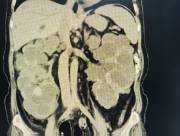

近日,西咸院区移植泌尿外科李智斌团队成功为一名复杂肾病患者同期实施“多囊肾切除+肾上腺肿瘤切除+肾移植术”。此次多术式联合手术,一次性解决了患者终末期肾病、巨大多囊肾及右侧肾上腺肿瘤三大难题,标志着欧美视频

在复杂器官移植领域取得了重要的突破。

该患者病情复杂,巨型多囊肾已对周围脏器造成严重压迫,同时肾上腺肿瘤导致原发性醛固酮增多症需长期口服药物治疗,而异体肾移植更是对手术精度和围术期管理有着极高要求。

手术过程中,李智斌带领团队沉着应对,精准解剖,在切除右侧巨型多囊肾和病变肾上腺之后,快速完成血管吻合,确保移植肾即刻恢复血流。整个手术历时近5小时,术后未出现并发症,现已转入普通病房康复。